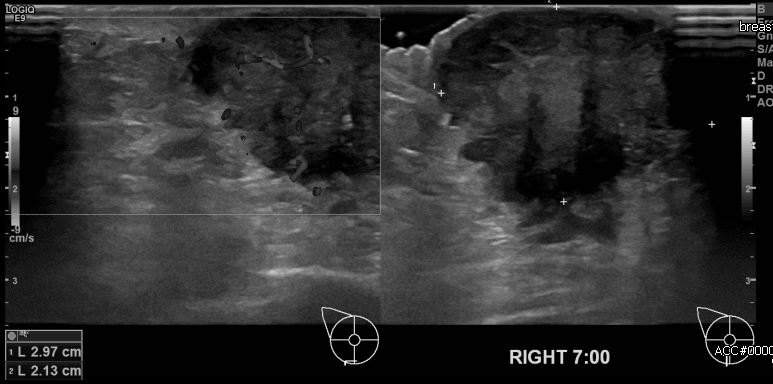

상기환자 유측 만져지는 멍울로 내원하신 80대 여성분으로 본원 초음파상 우측 7시 방향에 만져지는 의심스러운 멍울 조직검사 시행하여 침윤성 유관암 진단 되었습니다.